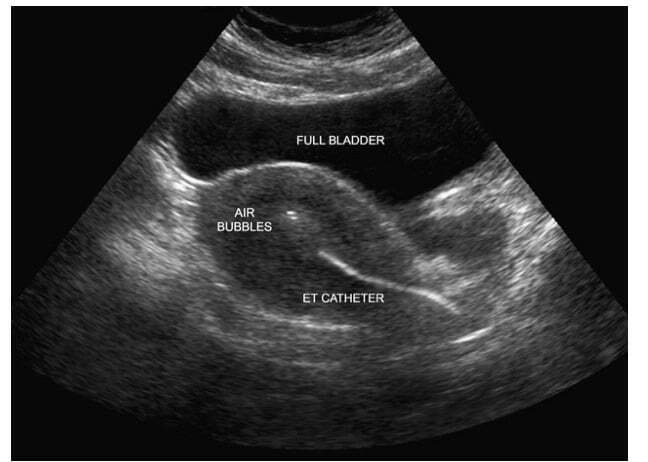

На 5 сутки ( а можно и на 3, и на 2) происходит перенос эмбриона в полость матки с помощью специального катетера. Безболезненно и быстро.

Пузырьки воздуха вводятся в катетер перед и после жидкости с эмбрионом, это нужно, чтобы видеть место переноса на УЗИ. Эмбрион плавает в жидкости между пузырьками и в дальнейшем имплантируется (Или не имплантируется) в ткань эндометрия и развивается беременность.